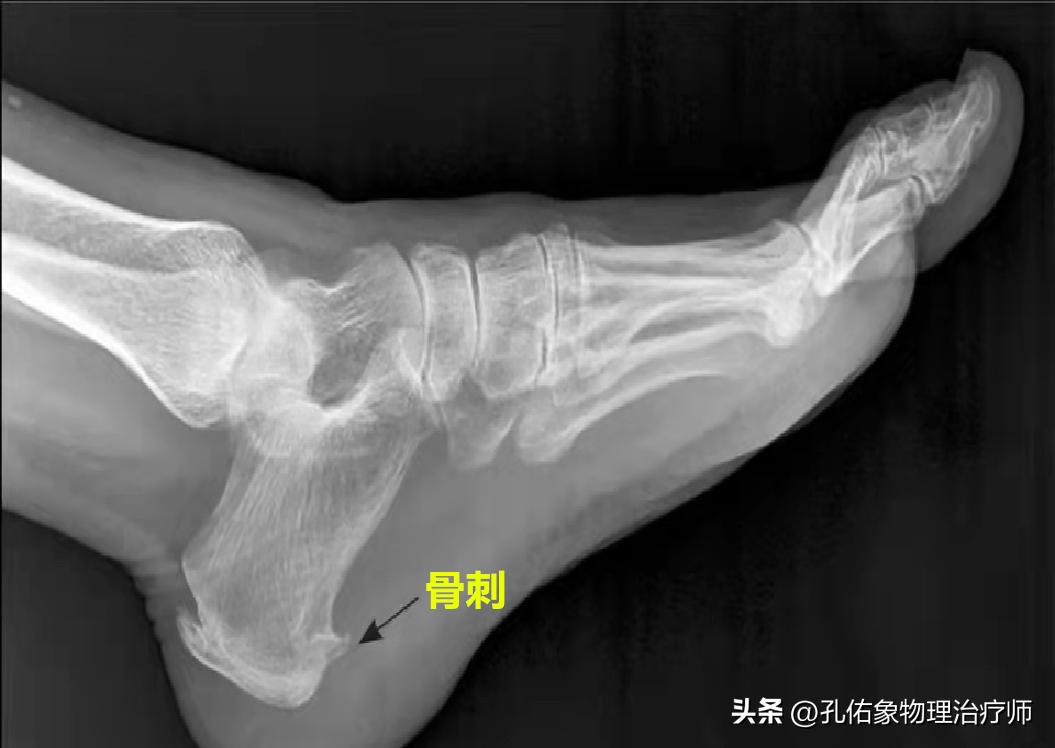

这一般和足底筋膜有关,或许有些人会到医院拍片,显示跟骨有骨刺,总误认为脚跟的疼痛是骨刺引发的。这是一种错误的认知,望大家重视。

在我们跟骨的位置,是足底筋膜附着点,若是长期反复牵拉,就会导致筋膜附着点张力大,逐渐形成钙化点,所以在片子的静态影像中会看到骨刺,其实,这个位置的筋膜早已出现微小撕裂伤,有水肿、炎症。